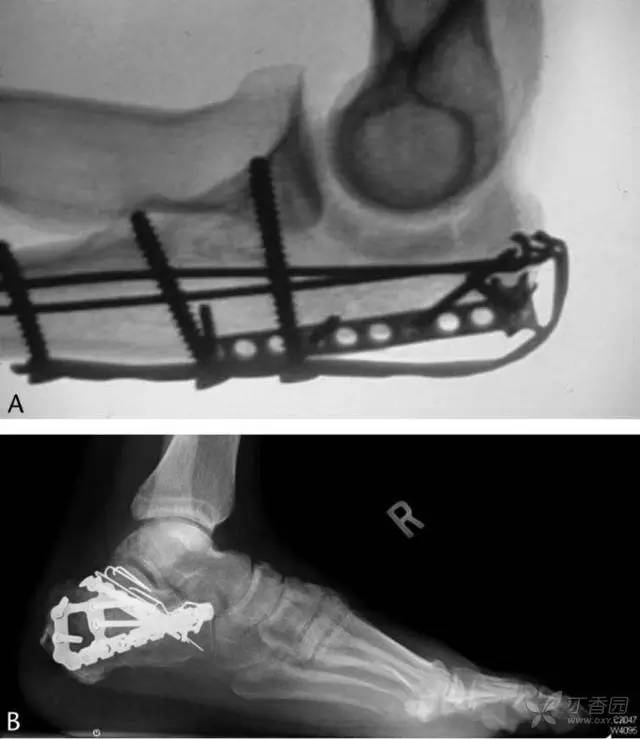

术后至终末随访平均 2.26 年(12-46 个月)。X 线片显示无一例出现克氏针移位,也没有发生克氏针相关的疼痛。10 例患者由于钢板等原因需要拆除内固定物,这些患者共有 40 根克氏针均顺利拆除无任何并发症。

图 8 克氏针应用实例。A,鹰嘴骨折;B,跟骨骨折。